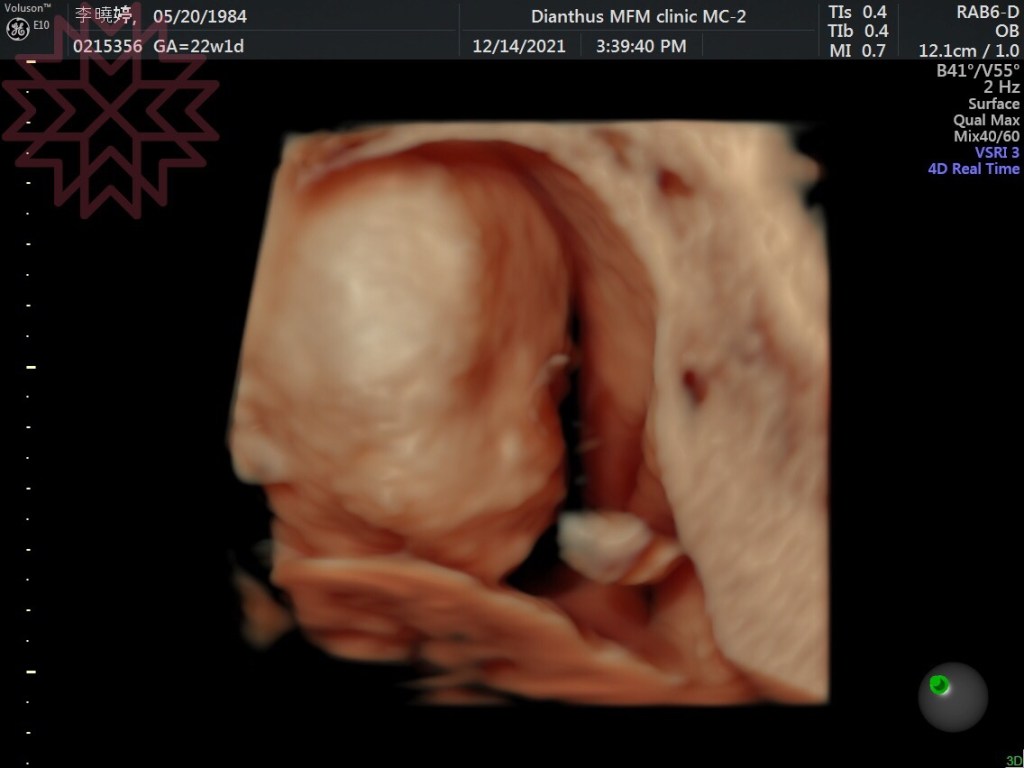

白雲20週,6個月了,剛做完【非侵入性胎兒梁色體檢測】(NIPT)目前為止都是非常健康。接下來過幾週,就是高層次超音波、妊娠糖尿檢查,還有定期量血壓,以及每次的產檢是否都能過關!白雲阿,爸爸媽媽都很愛你喔,期待你平安健康的到來,藍天會是一個很棒的哥哥,負責任、有同理心、有自信的手足!白雲會是一個真誠、尊重、內心強大的男人,2個會相親相愛! !

媽媽覺得,白雲也是一樣秀氣

照太久(雖然才1小時)白雲直接轉身不給照(藍天是苦瓜臉)

爸爸說,白雲看起來比藍天還要胖一點